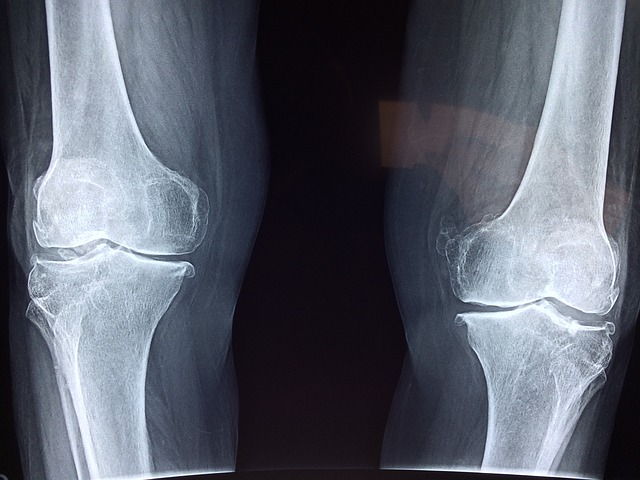

저는 몇년간 관절염으로 고생을 하다가 지금은 관절 통증을 거의 없애고 의사에게도 완치에 가깝다는 소견을 들은 사람입니다. 오늘은 제가 관절염을 고치는데 쓴 치료법, 운동, 영양제 등에 대해서 모두 알려드리도록 하겠습니다.